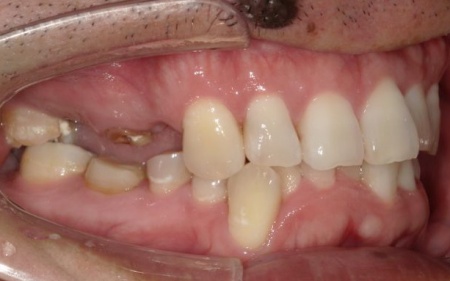

40代男性 温存が難しい複数の歯を抜いてインプラントブリッジで修復した症例

「ブリッジが外れたまま放置していた。また、前歯が欠けているのが気になる」とご相談いただきました。

拝見したところ、上左右の奥歯には、歯が失われていたり欠けたりしている部位が複数確認されました。

患者様によると、以前上顎にはブリッジ(両隣の歯を支えとして欠損部を補う装置)が装着されていましたが、10年前に外れたきりそのままの状態で過ごしていたとのことでした。

痛みがなかったため、とくに治療は受けていなかったようですが、以前から前歯の一部が欠けていることが気になっており、見た目や将来のお口の健康に不安を感じていたそうです。

そこで、詳しく検査を行った結果、欠けたり傷んだりしている歯が複数見つかり、さらに歯茎や歯を支える骨にも問題が生じていました。

とくに、右上奥歯は前から4番目と6番目の歯、左上奥歯は前から4番目・5番目・6番目・8番目の歯が著しく傷んでおり、温存が難しいと考えられます。

また、右下の一番奥の歯(親知らず)は歯の根だけが残り、細菌感染が広がるリスクが高い状態です。

その一方で、上前歯や右下奥歯は、適切な処置を行うことで温存できる歯も複数確認できました。